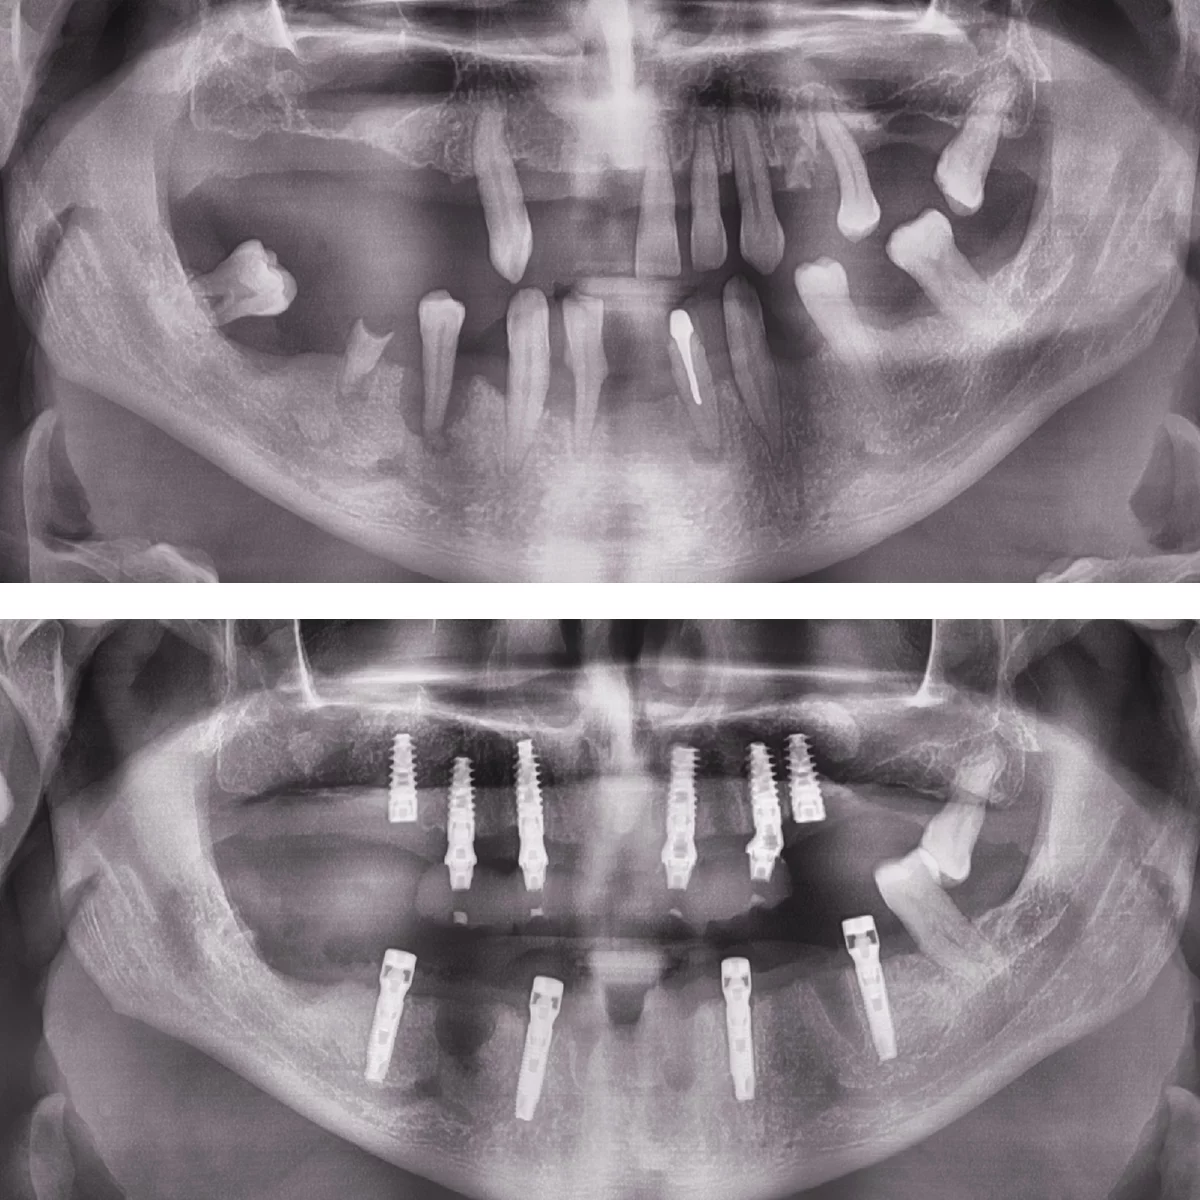

Dinți Ficși în 8-24 de ore pe implanturi dentare cu tehnica All-on-4/All-on-6 este cea mai eficientă și rapidă metodă de restaurare totală a danturii.

Intervenția chirurgicală explicată

Care sunt etapele până la efectuarea intervenției de dinți ficși

- Intervenția chirurgicală